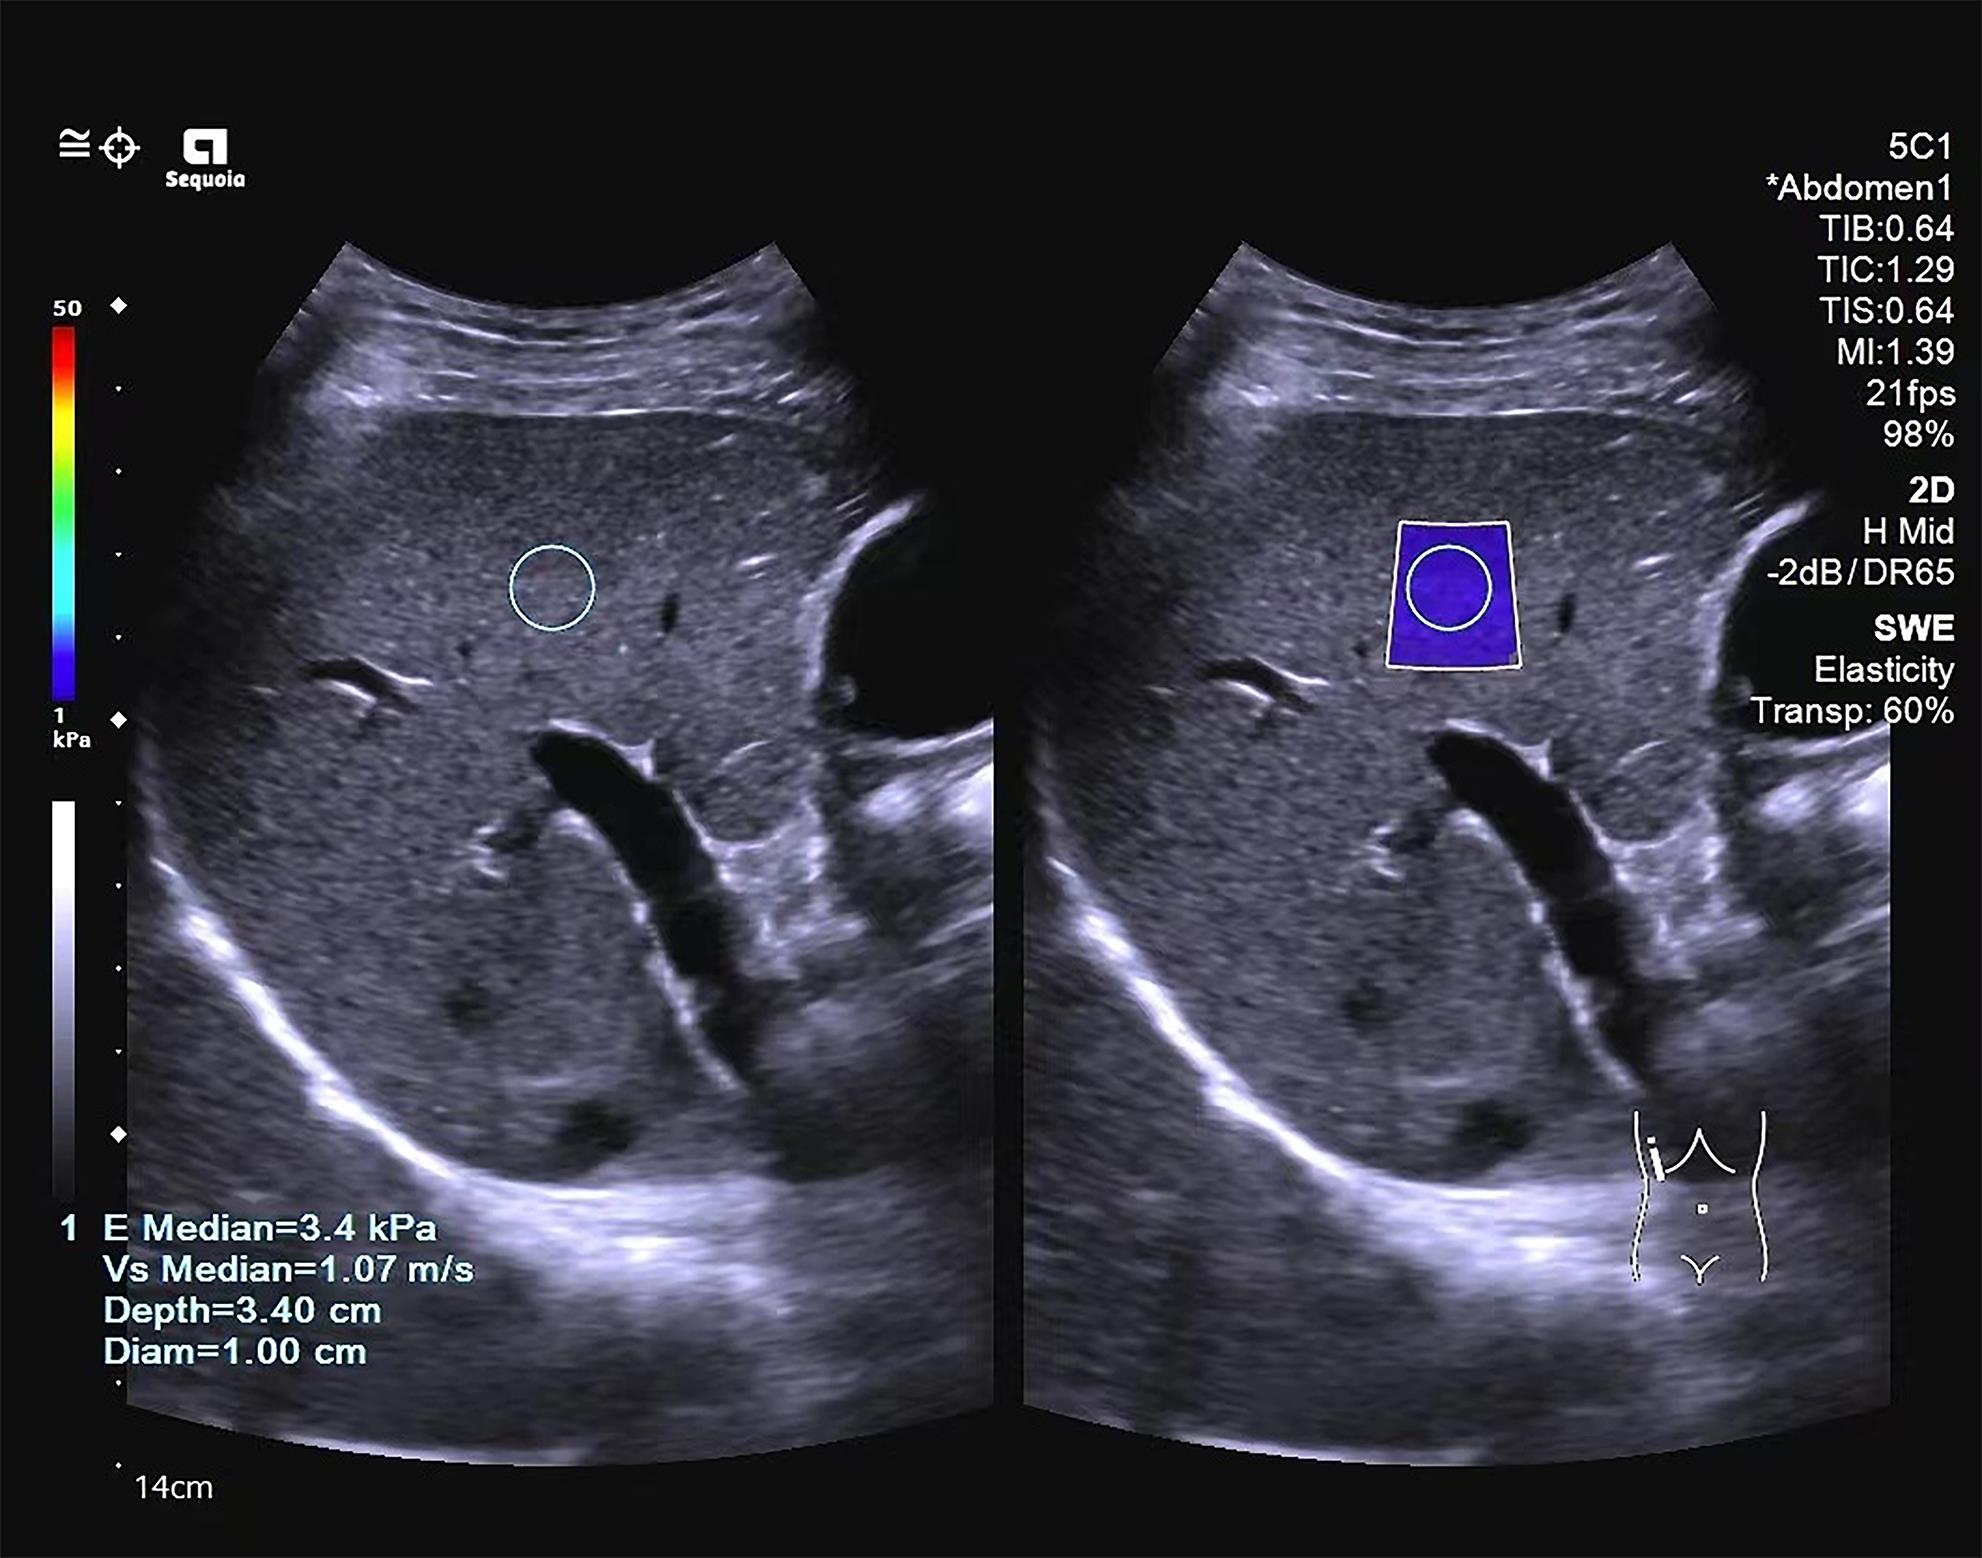

•   Objective  To investigate the value of two-dimensional shear wave elastography (2D-SWE) or serological models used alone or in combination in determining the stage of liver fibrosis in patients with chronic hepatitis B.  Methods  A retrospective analysis was performed for the clinical data of 327 patients with chronic hepatitis B who were admitted to Mengchao Hepatobiliary Hospital of Fujian Medical University from August 2020 to August 2022 and underwent 2D-SWE and liver histopathological examination, including sex, age, serological markers, and 2D-SWE results. According to the degree of liver fibrosis, they were divided into S0-S1, S≥2, S≥3, and S=4 groups, and the serological models were calculated based on serological markers. A Spearman correlation analysis was used to investigate the correlation of 2D-SWE and serological models with liver fibrosis stage; the receiver operating characteristic curve was plotted with the results of liver histopathology as the standard to compare the efficiency of each parameter used alone or in combination in determining the stage of liver fibrosis; the Delong test was used to investigate the difference between different methods.  Results  Liver stiffness measurement measured by 2D-SWE was strongly correlated with the stage of liver fibrosis (r=0.741, P<0.001), and as for the serological model, six markers (APRI, FIB-4, GPR, GP, RPR, and S index), other than AAR, were positively correlated with the stage of liver fibrosis (all P<0.001). 2D-SWE had an area under the ROC curve (AUC) of 0.878, 0.932, and 0.942, respectively, in the diagnosis of S≥2, S≥3, and S=4 liver fibrosis (all P<0.001), with an optimal cut-off value of 6.9 kPa, 7.9 kPa, and 9.4 kPa, respectively. Among the serological models, APRI had the largest AUC of 0.788 and 0.875, respectively, in the diagnosis of S≥2 and S=4 liver fibrosis, and S index had the largest AUC of 0.846 in the diagnosis of S≥3 liver fibrosis. In the diagnosis of S≥2, S≥3, and S=4 liver fibrosis, 2D-SWE combined with APRI increased the AUC values to 0.887, 0.938, and 0.950, respectively, and 2D-SWE combined with S index increased the AUC values to 0.879, 0.935, and 0.941, respectively, while there were no significant differences between 2D-SWE and the above combinations (P>0.05).  Conclusion  2D-SWE has a better diagnostic efficacy than the above seven serological models in determining liver fibrosis stage. The serological models have a certain diagnostic value, among which APRI and S index have a relatively high diagnostic value. There is no significant difference between 2D-SWE and 2D-SWE combined with serological models, and such combinations cannot significantly improve diagnostic efficiency. Therefore, further studies are needed to explore new combinations of diagnostic methods.